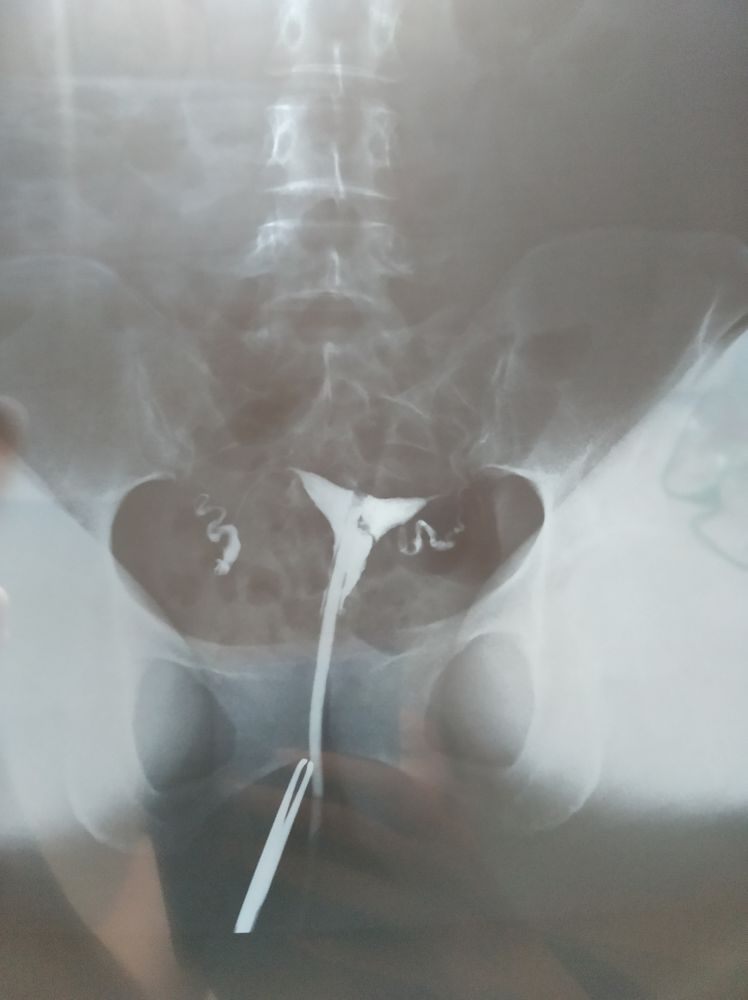

Кто разбирается, по фото рентгена что можете сказать?

Ну вроде контраст с обеих сторон в брюшной полости, значит трубы проходимы.

Явно не седловидная матка . При седловидности дно матки прогнуто сильно в низ , у вас такого нет. Левый яичник действительно гдето за маткой ,но это лишь его расположение ,только и всего ,если при гсг контраст проходил по трубам значит все ок.

Фанта, когда сильно прогнута это уже двурогая, а так похожа на седловидную, но это абсолютно не страшно

Мария, ну я видимо загнула со словом "сильно"😀 если совсем сильно то ла , двурогая, а если значительнее чем на рентген выше то седловидная